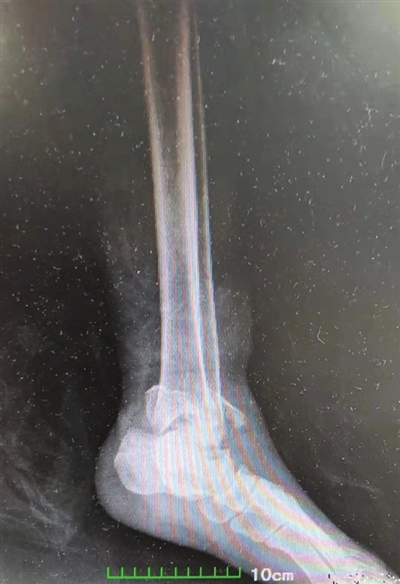

据刘先生介绍,今年9月中旬,他驾车外出途中不慎遭遇车祸伤及左足踝部,以为只是踝关节挤压了一下,休息一下就好。谁知近一个小时的时间后,刘先生左足踝关节不仅没有好转的迹象,反而疼痛持续加剧,被家人紧急送医。市第一人民医院骨外科主任刘昌余接诊后,立即为刘先生完善了相关检查。根据CT检查结果,诊断刘先生为为左踝关节Pinon骨折,如果不赶快进行救治,将落下终身残疾。

由于pilon骨折是指累及胫距关节面的胫骨远端骨折。而刘先生属于于pilon骨折中Ⅲ型,即关节面粉碎移位及粉碎程度较严重,手术难度较大,该科立即电话联系了武汉中南医院足踝外科中心主任祝少博,并组织专家通过远程与其进行了科内会诊、讨论,确定了在局部麻醉下先期为患者行跟骨牵引,并进行骨科常规护理、给予止血、消肿、止痛,待踝关节肿胀减轻后再行左胫腓骨下段粉碎性骨折开放复位钢板螺钉内固定术的整体方案。

手术当日,祝少博主任亲临手术现场,在市第一人民医院骨外科医生密切配合下,亲手为刘先生进行了手术。手术时长5个半小时,最终,刘先生的左踝部位得到完美修复。在市第一人民医院骨外科医护人员的精心护理下,目前刘先生已康复出院,这才有了本文开头的一幕。